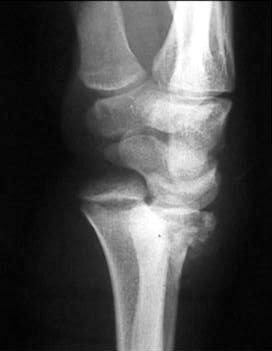

Больной из соседнего района 17 лет получил травму 8 09 03. Перелом по классификации E.Muller -В2

Неполный внутрисуставной перелом лучевой, тыльного края (Barton) Наложена гипсовая повязка рис 08 09. Через месяц на контрольной рентгенограмме найдено вывих л\з сустава. Рентгенограмма при обращении в нашу больницу 21 10 03 рис 21 10. На данные момент имеется умеренно выраженная контрактура, умеренные нейровегетативные нарушения.Обдумываем несколько вариантов лечения:1) Продолжить консервативное лечение и провести артродез, если останется болевой синдром.2) Провести открытую репозицию, устранить вывих, фиксировать отломок пластиной по тыльной поверхности.3) Провести артродез в лучезапястном суставе